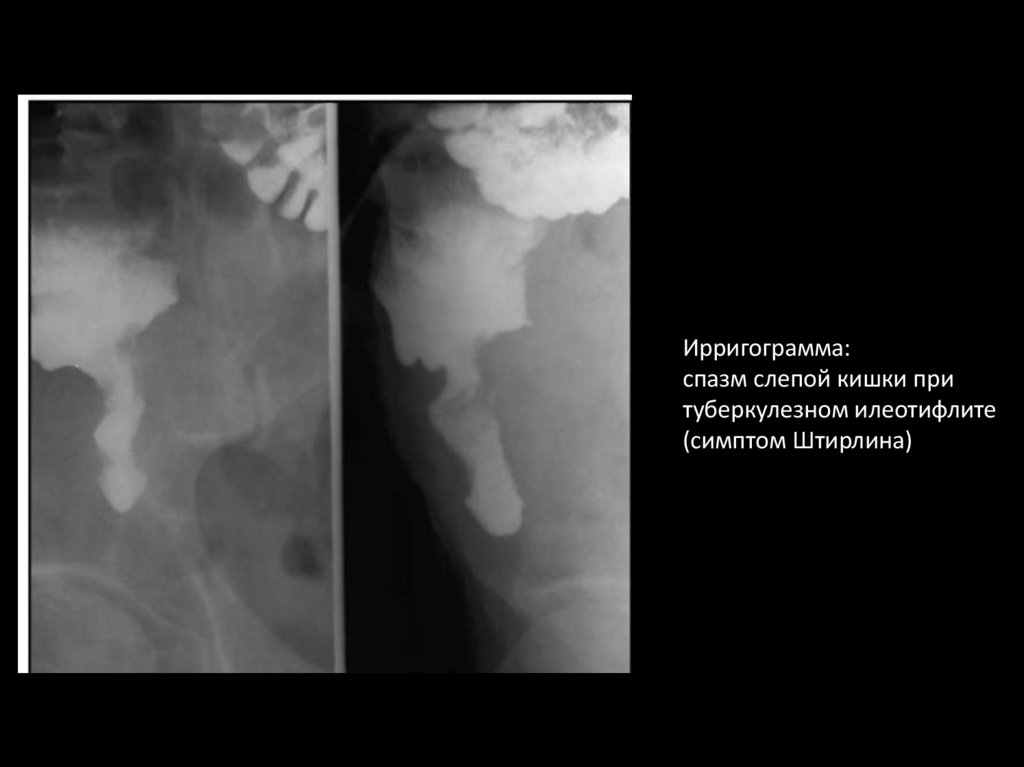

80.

Ирригограмма:

спазм слепой кишки при

туберкулезном илеотифлите

(симптом Штирлина)